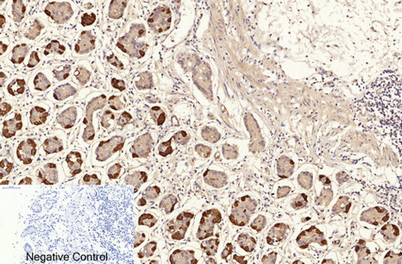

ÕŠ«õ┐ĪńöĄĶäæń½»ÕÆ©Ķ»ó

Õģ│µ│©ÕŠ«õ┐ĪÕģ¼õ╝ŚÕÅĘ

ÕŠ«õ┐Īµē½õĖƵē½Ķ┐×Õ┐ÖÕÆ©Ķ»ó

ÕŠ«õ┐Īµē½õĖƵē½Ķ┐×Õ┐ÖÕÆ©Ķ»ó